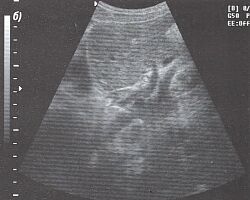

3.Техника получения подреберного среза печени. Помещаем датчик под правый нижний реберный край (рис. 3) и, легко нажимая на кожу, производим веерообразные движения сверху вниз и снаружи кнутри (рис. 4). Когда мы направляем датчик вверх, то видим печеночные вены (рис. 5) и изучаем сегментарное строение печени. Затем, направляя датчик немного вниз, можно увидеть вены воротной системы (рис. 6).